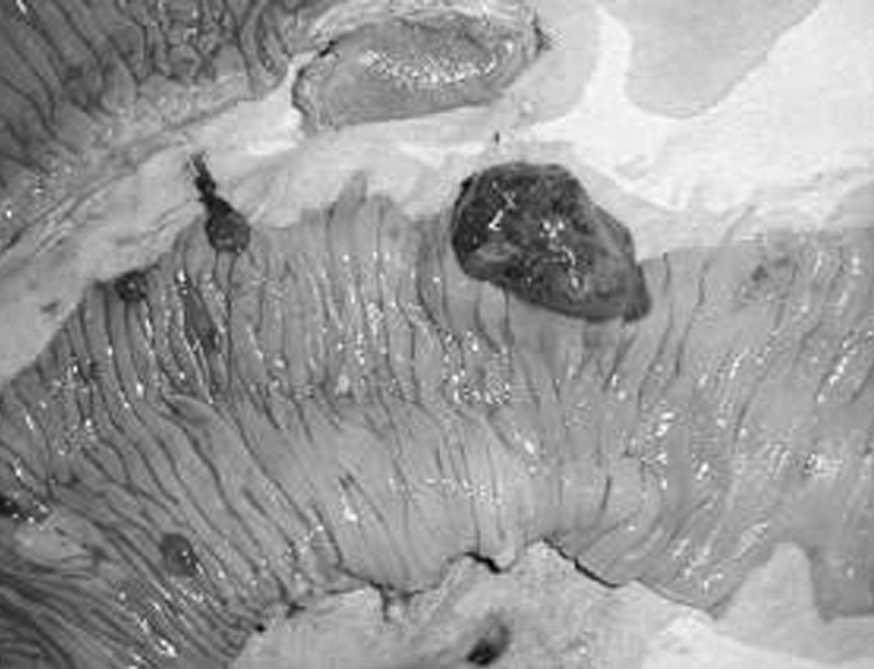

Varón de 30 años que ingresó por cefalea retroocular súbita, disminución del nivel de conciencia y vómitos. En la tomografía computarizada (TC) craneal se observaron hematomas agudos en los lóbulos occipitales, que se drenaron quirúrgicamente y se biopsiaron. En el postoperatorio presentó un cuadro de hemoptisis, hematemesis y rectorragia que le causaron anemia. En la radiografía de tórax se obtuvo imagen en "suelta de globos". Endoscopia digestiva alta: lesiones verrugosas y ulceradas gástricas sangrantes. Fue intervenido quirúrgicamente y se encontró una invaginación intestinal secundaria a lesiones tumorales intraluminares en el yeyuno (fig. 1); se realizó resección del segmento intestinal afectado, de una lesión interaortocava y una gastrectomía atípica. Falleció al quinto día. En el examen histológico se observó metástasis de coriocarcinoma en todas las piezas. La exploración testicular fue normal y las determinaciones de alfafetoproteína y betagonadotropina coriónica estaban elevadas.

Fig. 1. Imagen de lesiones tumorales intraluminales.